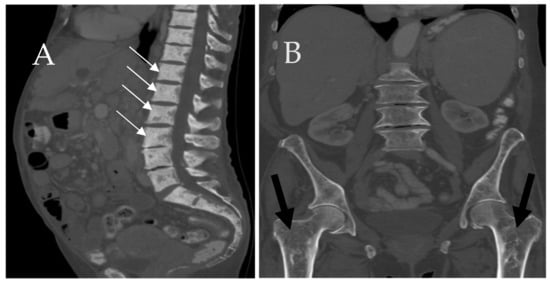

6.1. Skeletal

- Leone, A.; Criscuolo, M.; Gullì, C.; Petrosino, A.; Carlo Bianco, N.; Colosimo, C. Systemic mastocytosis revisited with an emphasis on skeletal manifestations. Radiol. Med. 2021, 126, 585–598. [Google Scholar] [CrossRef] [PubMed]

- Fritz, J.; Fishman, E.K.; Carrino, J.A.; Horger, M.S. Advanced imaging of skeletal manifestations of systemic mastocytosis. Skelet. Radiol. 2012, 41, 887–897. [Google Scholar] [CrossRef] [PubMed]

- Barete, S.; Assous, N.; De Gennes, C.; Grandpeix, C.; Feger, F.; Palmerini, F.; Dubreuil, P.; Arock, M.; Roux, C.; Launay, J.M.; et al. Systemic mastocytosis and bone involvement in a cohort of 75 patients. Ann. Rheum. Dis. 2010, 69, 1838–1841. [Google Scholar] [CrossRef]

- Roca, M.; Mota, J.; Giraldo, P.; García Erce, J.A. Systemic mastocytosis: MRI of bone marrow involvement. Eur. Radiol. 1999, 9, 1094–1097. [Google Scholar] [CrossRef]

- Ozturk, K.; Cayci, Z.; Gotlib, J.; Akin, C.; George, T.I.; Ustun, C. Non-hematologic diagnosis of systemic mastocytosis: Collaboration of radiology and pathology. Blood Rev. 2021, 45, 100693. [Google Scholar] [CrossRef]